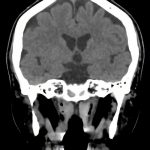

下垂体腺腫

断層撮影

手術前1

No.’16_18 手術前1